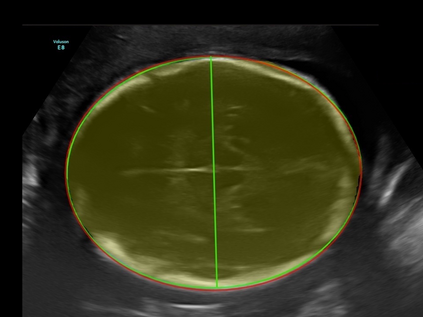

In this paper, we propose an end-to-end multi-task neural network called FetalNet with an attention mechanism and stacked module for spatio-temporal fetal ultrasound scan video analysis. Fetal biometric measurement is a standard examination during pregnancy used for the fetus growth monitoring and estimation of gestational age and fetal weight. The main goal in fetal ultrasound scan video analysis is to find proper standard planes to measure the fetal head, abdomen and femur. Due to natural high speckle noise and shadows in ultrasound data, medical expertise and sonographic experience are required to find the appropriate acquisition plane and perform accurate measurements of the fetus. In addition, existing computer-aided methods for fetal US biometric measurement address only one single image frame without considering temporal features. To address these shortcomings, we propose an end-to-end multi-task neural network for spatio-temporal ultrasound scan video analysis to simultaneously localize, classify and measure the fetal body parts. We propose a new encoder-decoder segmentation architecture that incorporates a classification branch. Additionally, we employ an attention mechanism with a stacked module to learn salient maps to suppress irrelevant US regions and efficient scan plane localization. We trained on the fetal ultrasound video comes from routine examinations of 700 different patients. Our method called FetalNet outperforms existing state-of-the-art methods in both classification and segmentation in fetal ultrasound video recordings.